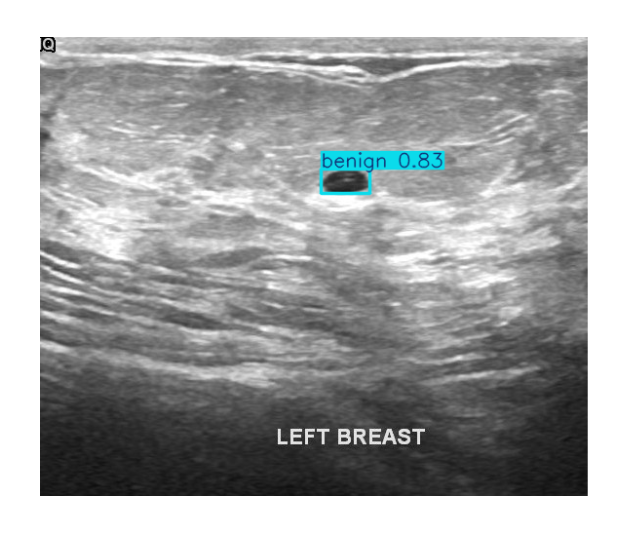

Supports multi-modal inputs including structured indicators, voice, dialogue, and imaging for comprehensive care.